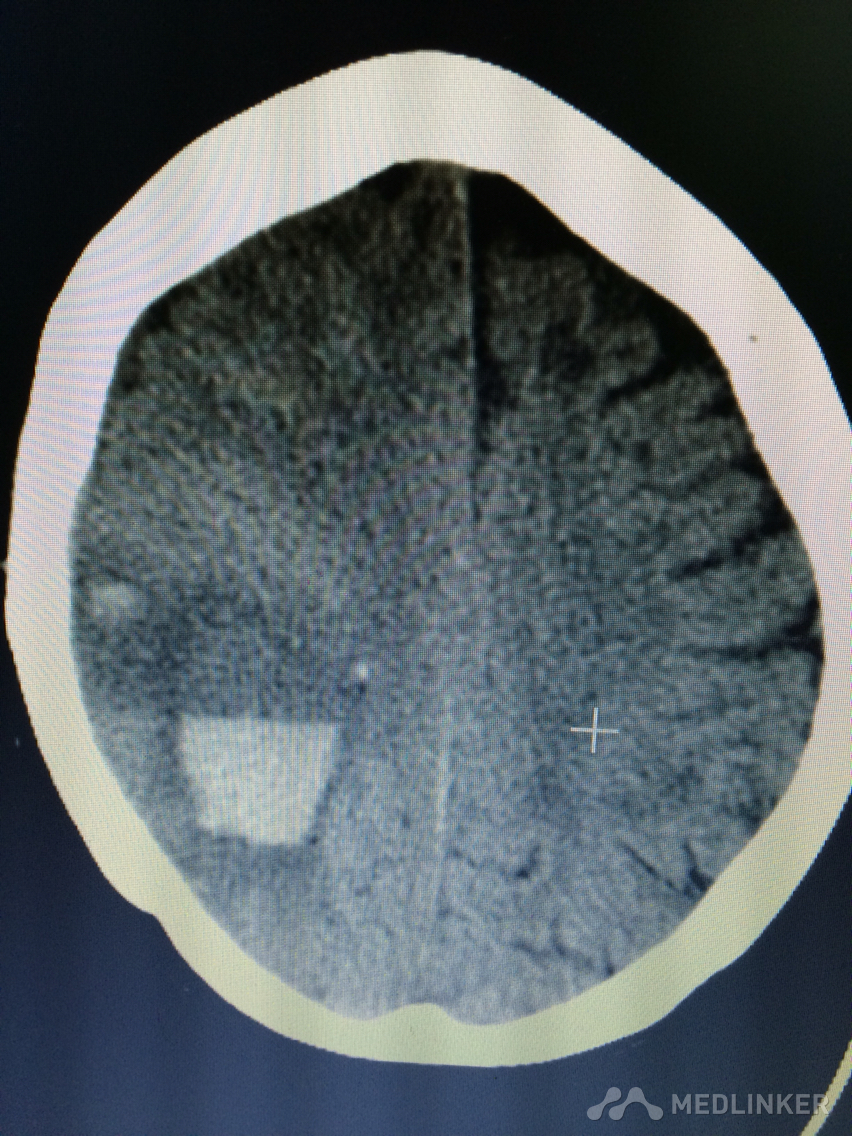

下面的CT考虑?

1天前,患者睡醒后出现反应迟钝,认知功能障碍,左侧肢体乏力。 既往无高血压病史,近期无外伤史。